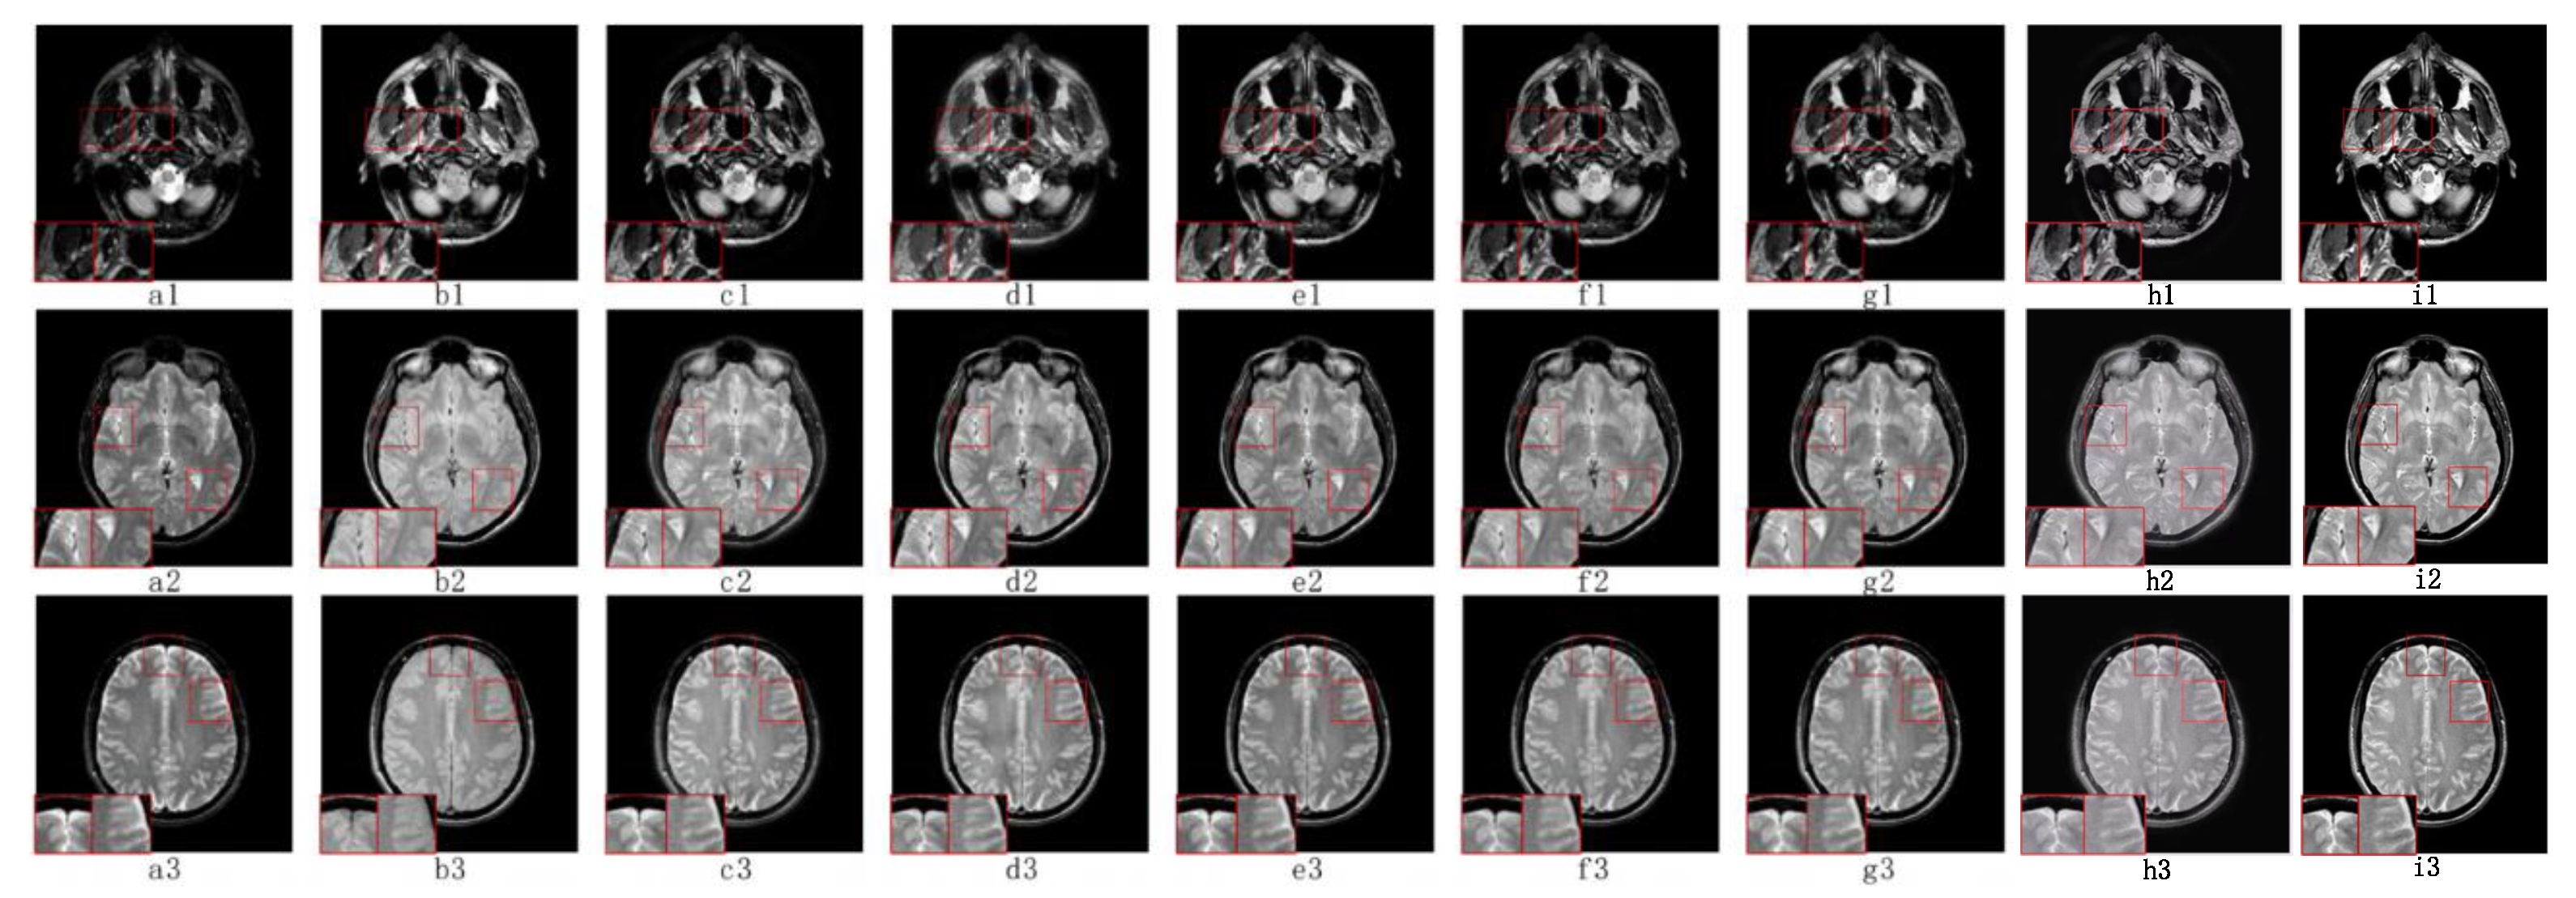

5.2. Visual Effects Analysis

5.2.2. Fusion Analysis on T2-PD

5.3. Objective Metrics Analysis